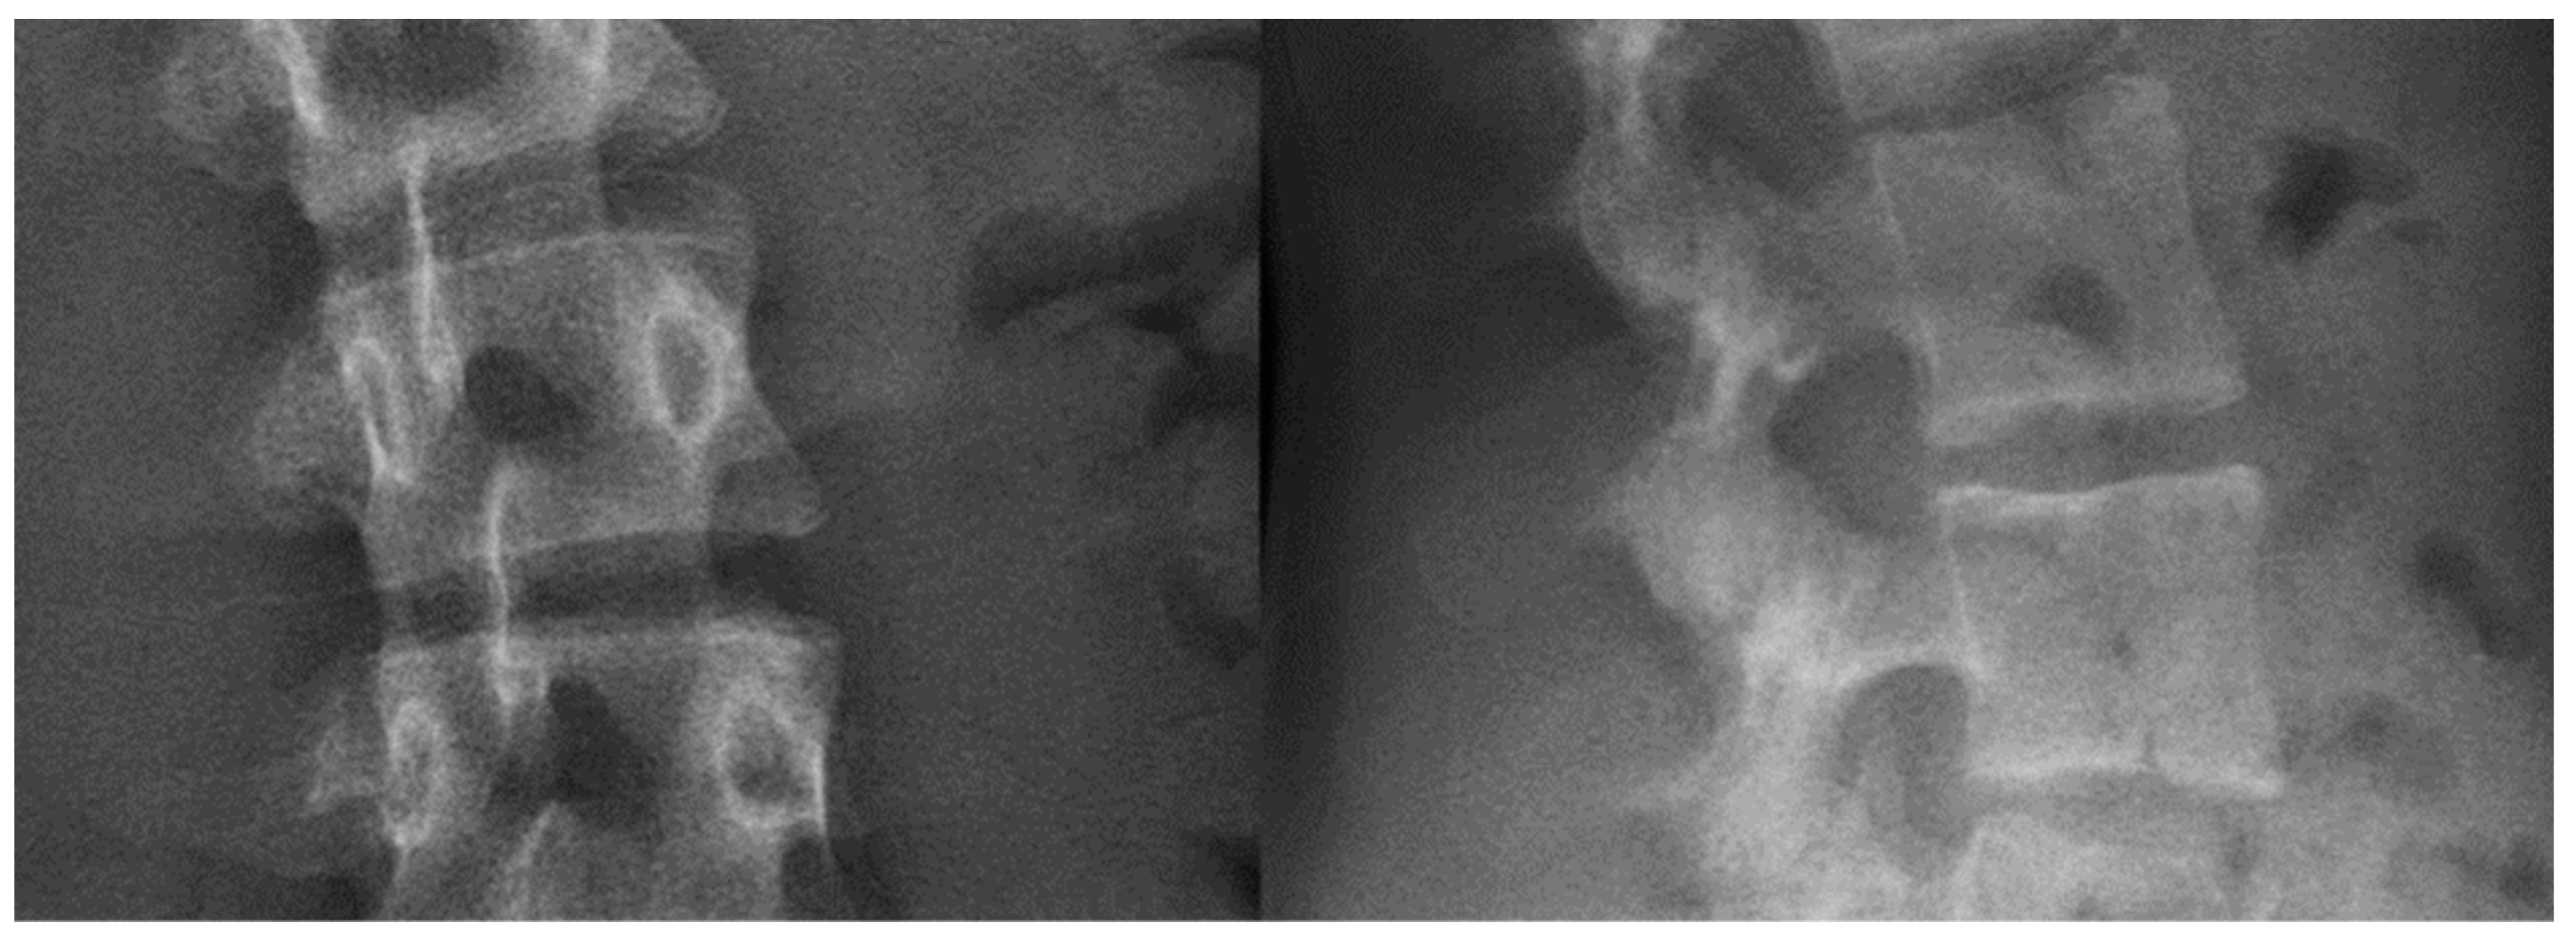

To model the vertebrae in a realistic manner, special consideration was given to the materials used for 3D printing. Firstly, a study was conducted to identify materials offering an appropriate radio-opacity. As the concept was to simulate the classical surgical care pathway followed by a patient with AIS, the 3D spine models needed to be imaged pre- and postoperatively, as well as potentially intra-operatively by a navigation system, and offer similar X-ray images to those of the actual patient. To reproduce the radiological appearance of the vertebrae, various materials were tested on 1-mm-thick sample plates (grey scale for each sample can be seen in Figure 2):

• Polylactic acid was too too opaque.

• Polylactic acid filled with 80% copper was transparent.

• Polylactic acid with 50% ceramic was identified to reproduce the radio-opacity of bone most closely.

Having selected the appropriate materials, the 3D printer settings were evaluated, in particular concerning the grey scales for the representation of cancellous bone (comparable to that of an actual vertebral X-ray). The following 3D printing settings were tested, employing a printing density between 20 and 30%:

• Filling “quarter cubic 45°” (pre-set in the 3D printer);

• Filling “hole’s infill” (pre-set in the 3D printer);

• Filling “personalized vertical grid 5°” (customized).

Three vertebrae (each 3D-printed with one of the above settings) were then imaged with EOSedge® (the latest EOS imaging device). Figure 3 shows that the customized filling “vertical grid 5°” setting obtains the most realistic radiographic rendering, with a uniform texture of cancellous bone and a significant signal in cortical bone. Bi-planar X-ray images of actual patient vertebrae and the surrounding soft tissues are presented in Figure 4 for comparison.

Figure 2. Grey levels of 1-mm-thick sample plates with different materials: polyactic acid with 50% ceramic (left), polyactic acid filled with 80% copper (middle), and polyactic acid (right).

Figure 3. Bi-planar X-rays of three 3D-printed vertebrae, each resulting from different printer settings. From top to bottom: quarter cubic 45°, hole’s infill, and personalized vertical grid 5°.

Figure 4. Bi-planar X-rays of the spine of an actual patient.